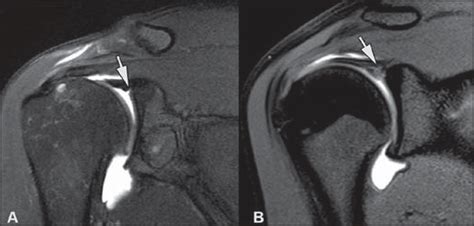

Diagnosing a labrum detachment shoulder involves a combination of medical history, physical examination, and imaging tests. The diagnostic process typically includes:

• Imaging Tests: Imaging studies such as X-rays, MRI, or CT scans can provide detailed images of the shoulder joint and help identify the location and extent of the labrum detachment.